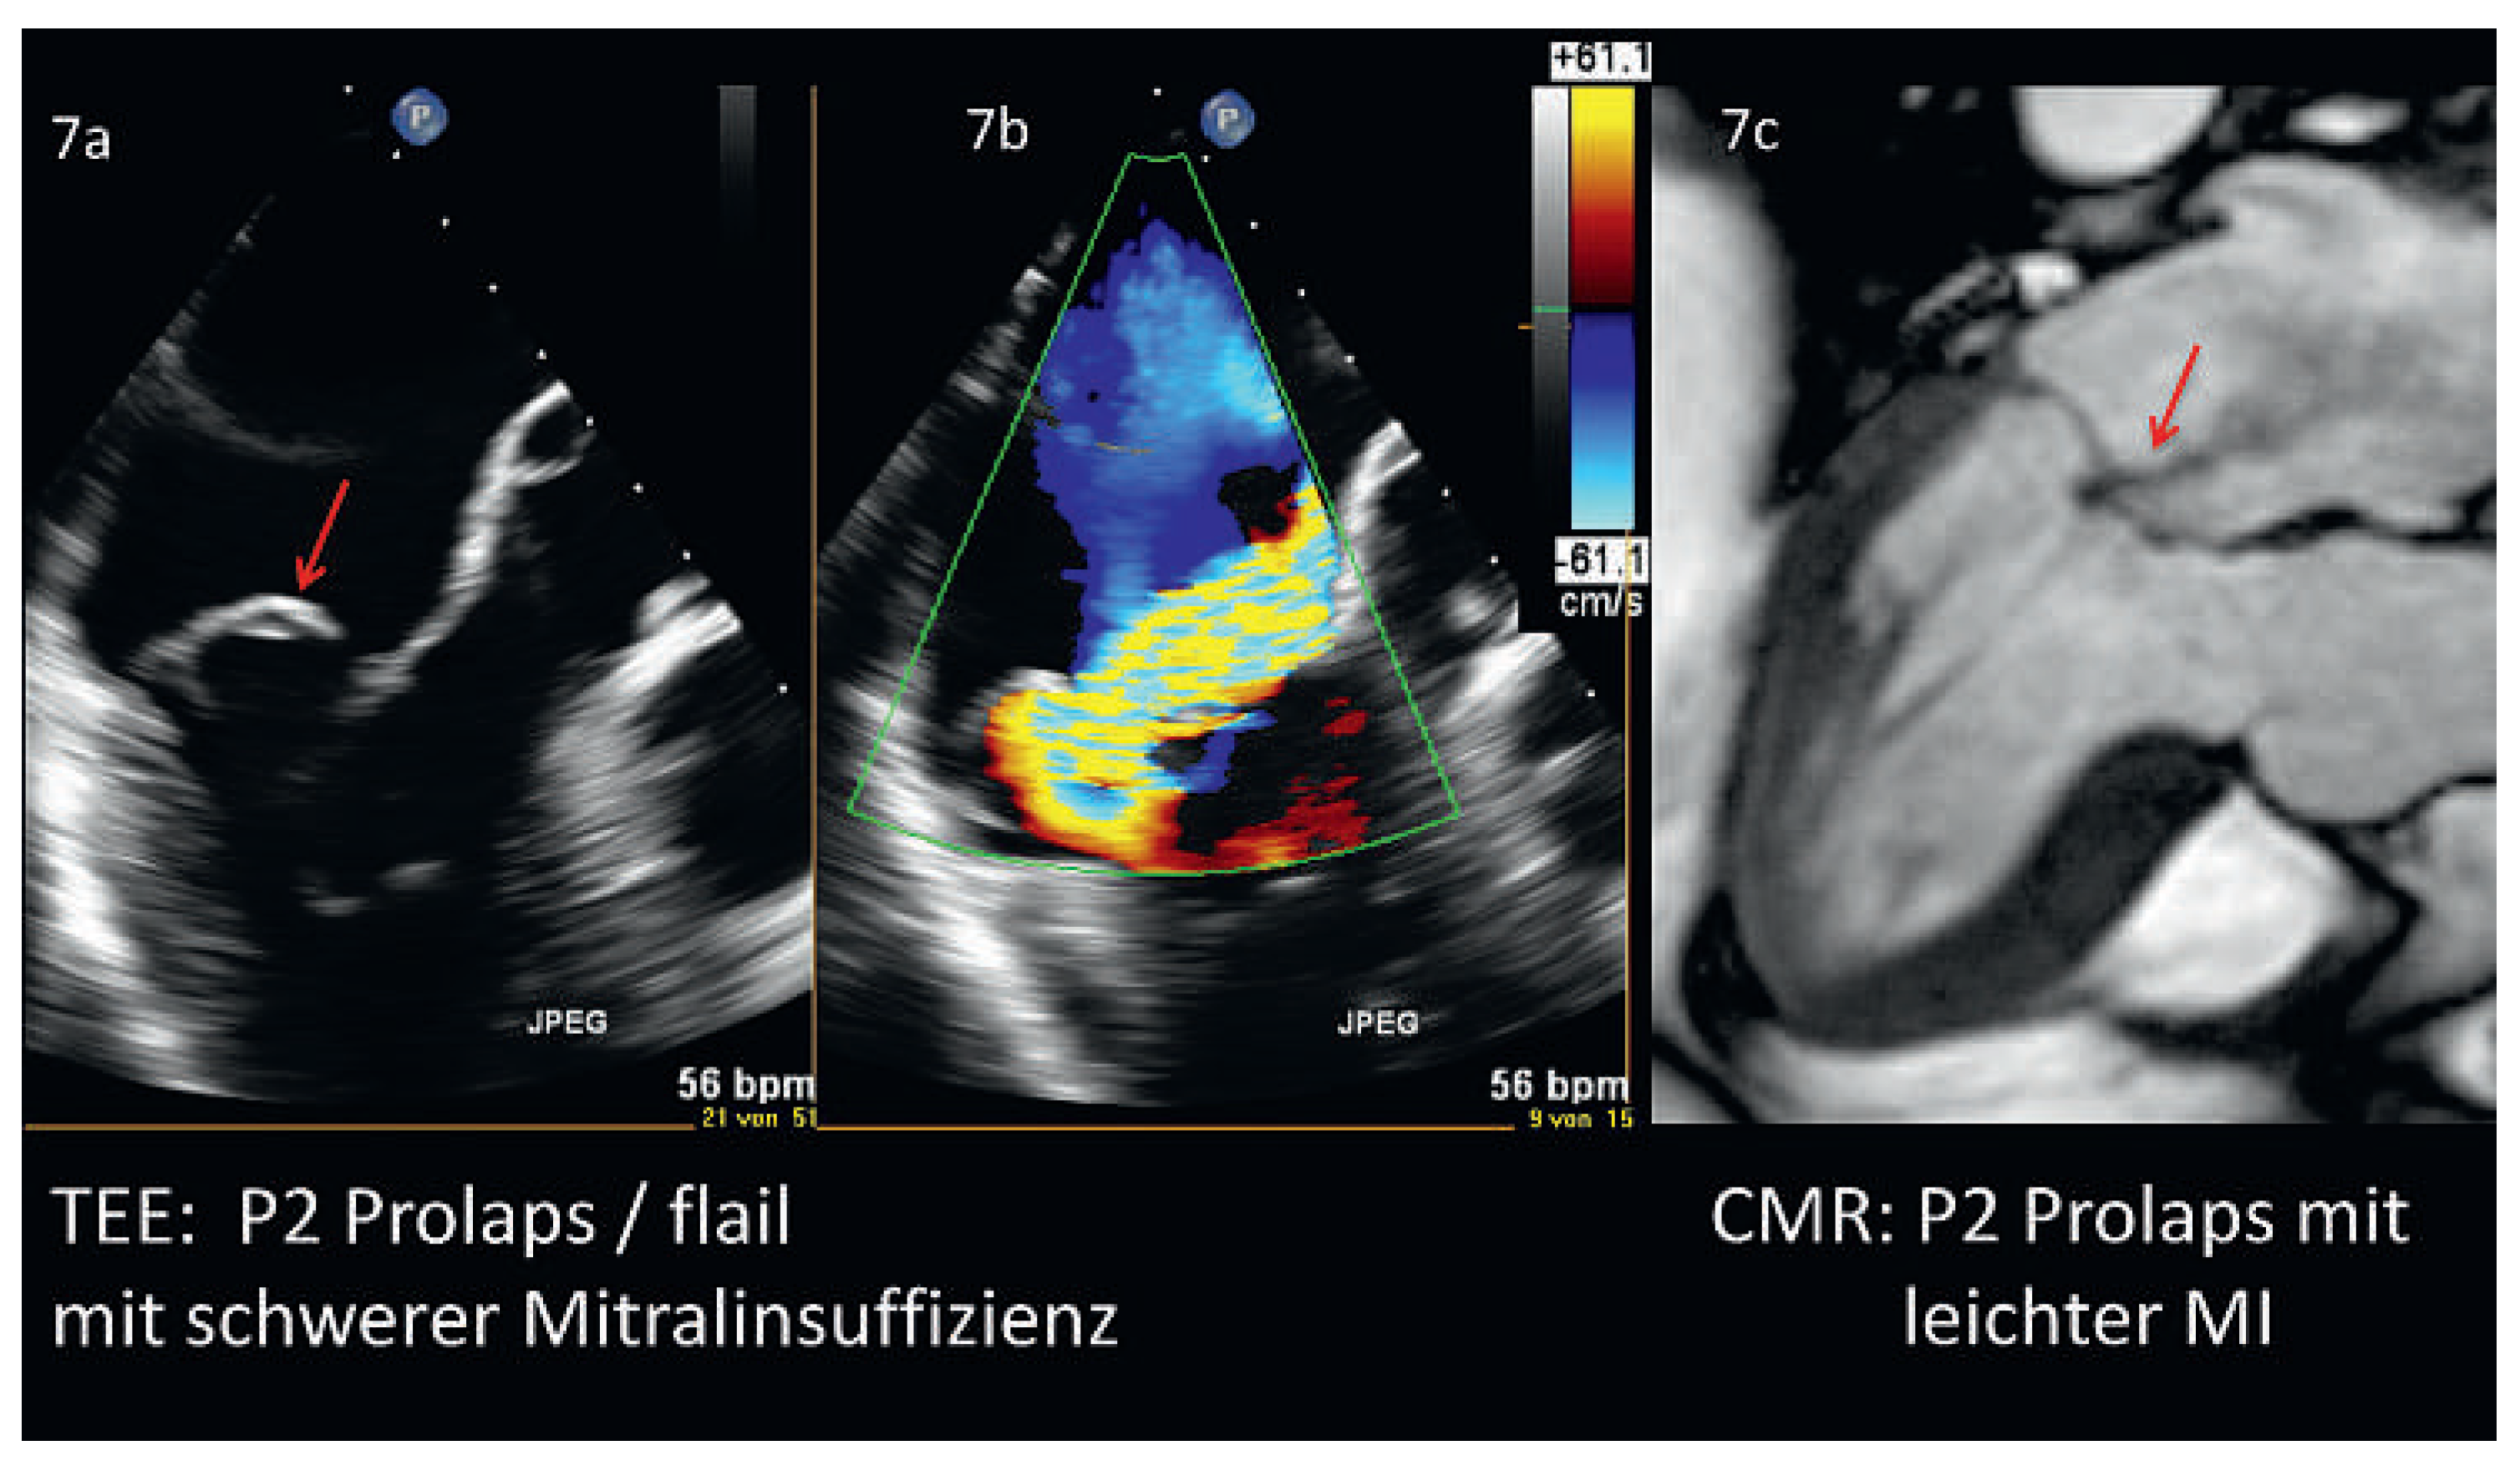

Abbildung 7. Mitralklappen-Prolaps (Segment P2) im Vergleich zwischen Echokardiographie und kardialer Magnetresonanztomographie. Abb. 7a: P2–Prolaps (roter Pfeil) mit Flail bei schwerer Mitralinsuffizienz im TEE. Abb. 7b: Schwere Regurgitation mittels Farb-Doppler. Abb. 7c: Im CMR erkennbarer Prolaps des P2–Segments (roter Pfeil) bei leichter Mitralinsuffizienz (Patient nicht identisch). Abkürzungen: CMR = kardiale Magnetresonanztomographie, MI = Mitralinsuffizienz, TEE = Transesophageales Echo.

Organische Mitralinsuffizienz

Aufgrund der hohen zeitlichen und räumlichen Auflösung ist die 2D-Echokardiographie das primäre diagnostische Instrument für den Mitralklappenprolaps (Abbildung 7a). Die 2D-Echokardiographie erlaubt es, auch abgerissene Sehnenfäden (Millimeterbereich) zu verfolgen, die während eines Herzschlages mehrfach hin und her schlagen, oder die Details der verschiedenen prolabierenden Segmente zu erkennen [36, 37]. Keine andere Untersuchungstechnik erlaubt solche Präzision am schlagenden Herzen. Gleichzeitig kann mittels der Farb-Doppler-Echokardiographie auch die Funktion beurteilt werden (Abbildung 7b). Insbesondere qualitative Aspekte werden dabei abgedeckt: Anzahl, Richtung und zeitliches Auftreten der verschiedenen Insuffizienzjets. Hingegen kann die Quantifizierung der Mitralinsuffizienz aufgrund der oben beschriebenen technischen Limitation (insbesondere durch unzutreffende geometrische Annahmen) anspruchsvoll oder unmöglich sein. Die Quantifizierung der Mitralinsuffizienz wird in Zukunft wohl in die Domäne der 3D-Echokardiographie fallen. Ein zusätzlicher Vorteil der 3D transesophagealen Echokardiographie (3D-TEE) liegt darin, dass die komplexe anatomische Struktur der Mitralklappe gut verständlich demonstriert werden kann. Die Übereinstimmung mit dem chirurgischen Befund ist dabei selbst bei komplexen Klappenveränderungen verblüffend [37]. Besonders bei der Quantifizierung der mit Morbus Barlow assoziierten multiplen Jets ist die 3D- der 2D-Technik überlegen [38]. Die 3D-TEE geschieht in Echtzeit (‚real-time’) und kann bei Geräten der neusten Generation auch mit dem Farb-Doppler-Modus ergänzt werden, was wiederum für die Identifikation von sehr exzentrischen Jets ein Vorteil sein kann. 3D-TEE zeigt gegenüber 2D eine höhere Sensitivität der einzelnen Segmente beim MKP sowie bei Chordaeruptur [37]. Die grosse Datenmenge, welche gleichzeitig vom Ultraschallgerät verarbeitet werden muss, bringt allerdings gerade bei der 3D transthorakalen Echokardiographie (3D-TTE) eine deutliche Einbusse der räumlichen Auflösung mit sich. Dies führt zu einer schlechteren Sensitivität für die Erkennung von prolabierenden Segmenten und Chordarupturen gegenüber der 3D-TEE [39], so dass die 3D-TTE im Alltag oft enttäuschend wenig anatomische Zusatzinformation bringt.

Auch die CMR kann für diagnostische Zwecke bei organischer Mitralinsuffizienz genutzt werden. Mittels direkter Visualisierung der ROA lässt sich prinzipiell eine funktionelle von einer organischen Ursache abgrenzen [35]. Die CMR hat eine mit Echokardiographie vergleichbare diagnostische Aussagekraft bei der Identifikation der verschiedenen Segmente eines Prolaps (Abbildung 7c). Bei der Darstellung von Sehnenfädenabrissen ist sie aufgrund schlechterer zeitlicher Auflösung der Echokardiographie unterlegen; überdies fehlt im Gegensatz zur Echokardiographie die Möglichkeit, die Schnittebene während der Untersuchung zu wechseln. Indiziert ist die CMR vor allem bei schlechter Ultraschallqualität [30].